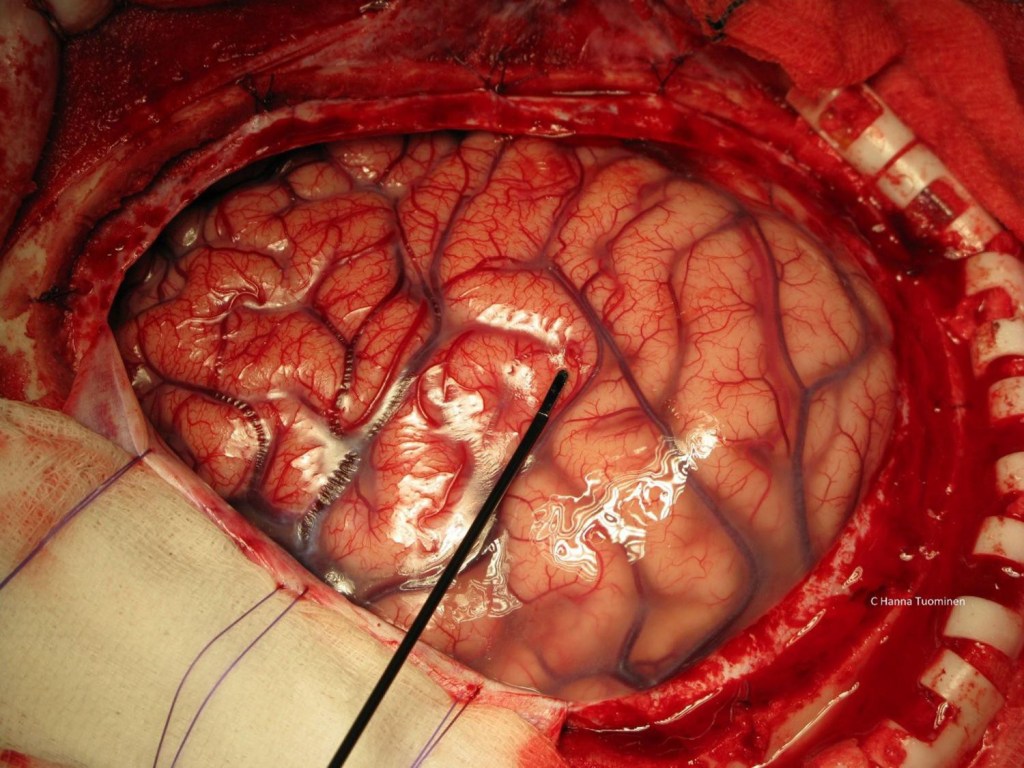

He found it! Dr. Smith found the bleeder. “Patty and Floseal” He says to me. I hand it to him and he dabs the vessel. No oozing. Then we wait and watch. He examines the rest of the brain making sure he did not miss any other bleeders. He irrigates and suctions all the old blood. While he was doing this, the brain tissue started to reveal its beauty.

The coils and swirls of pink and grey tissue wrapping around each other like a labyrinth. The tiny vessels were weaving in and out of those coils and swirls like ivy vines. It had a sheen now, a slight shimmer under the O.R. lights. As I watched it, it slightly pulsed. To this day it is one of my favorite sights. To see a brain pulse with life inside of someone’s head is such a life-changing experience. It’s complexity and power is overwhelming. It is like a pearl, a fragile pearl guarded by a hard armored shell. It is so soft and susceptible yet controls everything that we are and makes us who we are. Though all of us look alike inside, like a pearl, our brains are unique and signature. It is our guarded treasure. So, every time I see those intricate swirls and the pulse of life when I look at a brain, it humbles me and enlightens me. What incredible creatures we are!

The patient’s brain appeared dry. It had stopped bleeding. Dr. Smith was able to save this pearl, this brain, this mother, aunt, or sister. I began to hand him 4-0 neurolon sutures for him to close the dura. The thin, delicate tissue of the dura slides back on top of the brain like a satin sheet tucking it in for the night. Each stitch securing the dura tucks the brain in tighter and tighter. Good night precious pearl, stay safe and warm.